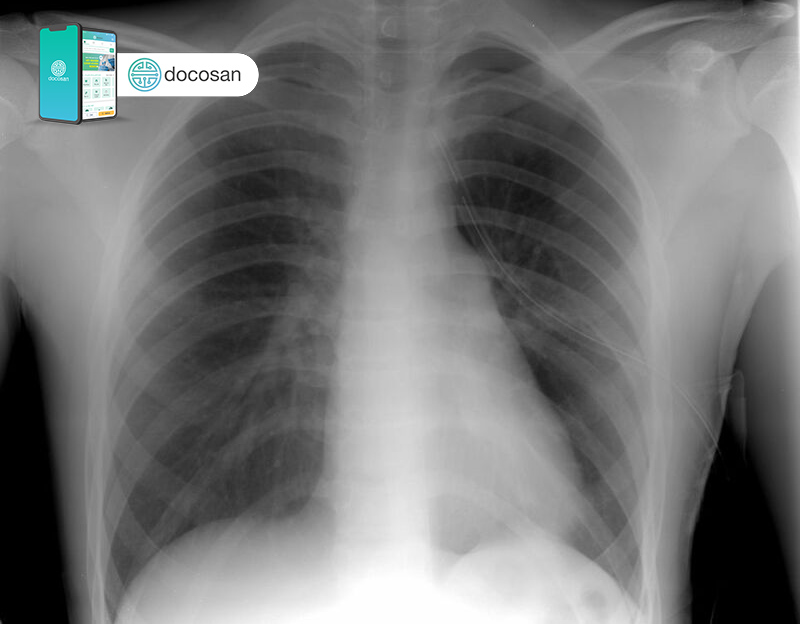

Khí phế thũng là tình trạng khó thở ở bệnh nhân gây ra bởi những tổn thương ở phổi. Ở những bệnh nhân bị khí phế thũng, các túi khí ở trong phổi (phế nang) bị tổn thương. Lâu dần, nhưng tổn thương này sẽ làm túi khí bị vỡ ra, tạo ra những khoảng trống ở trong phổi và làm giảm diện tích bề mặt phổi. Khi người bệnh thở, do phế nang hoạt động không còn ổn định và lượng không khí cũ bị mắt kẹt ở trong phổi, không còn chỗ cho những luồng không khí mới trong lành đi vào nữa.

- Xuất hiện những lỗ thủng lớn trên phổi: tình trạng khí phế thũng sẽ làm tạo nên những khoảng trống lớn ở phổi, làm suy giảm diện tích phổi. Chúng còn gia tăng nguy cơ tràn khí màng phổi ở người bệnh.